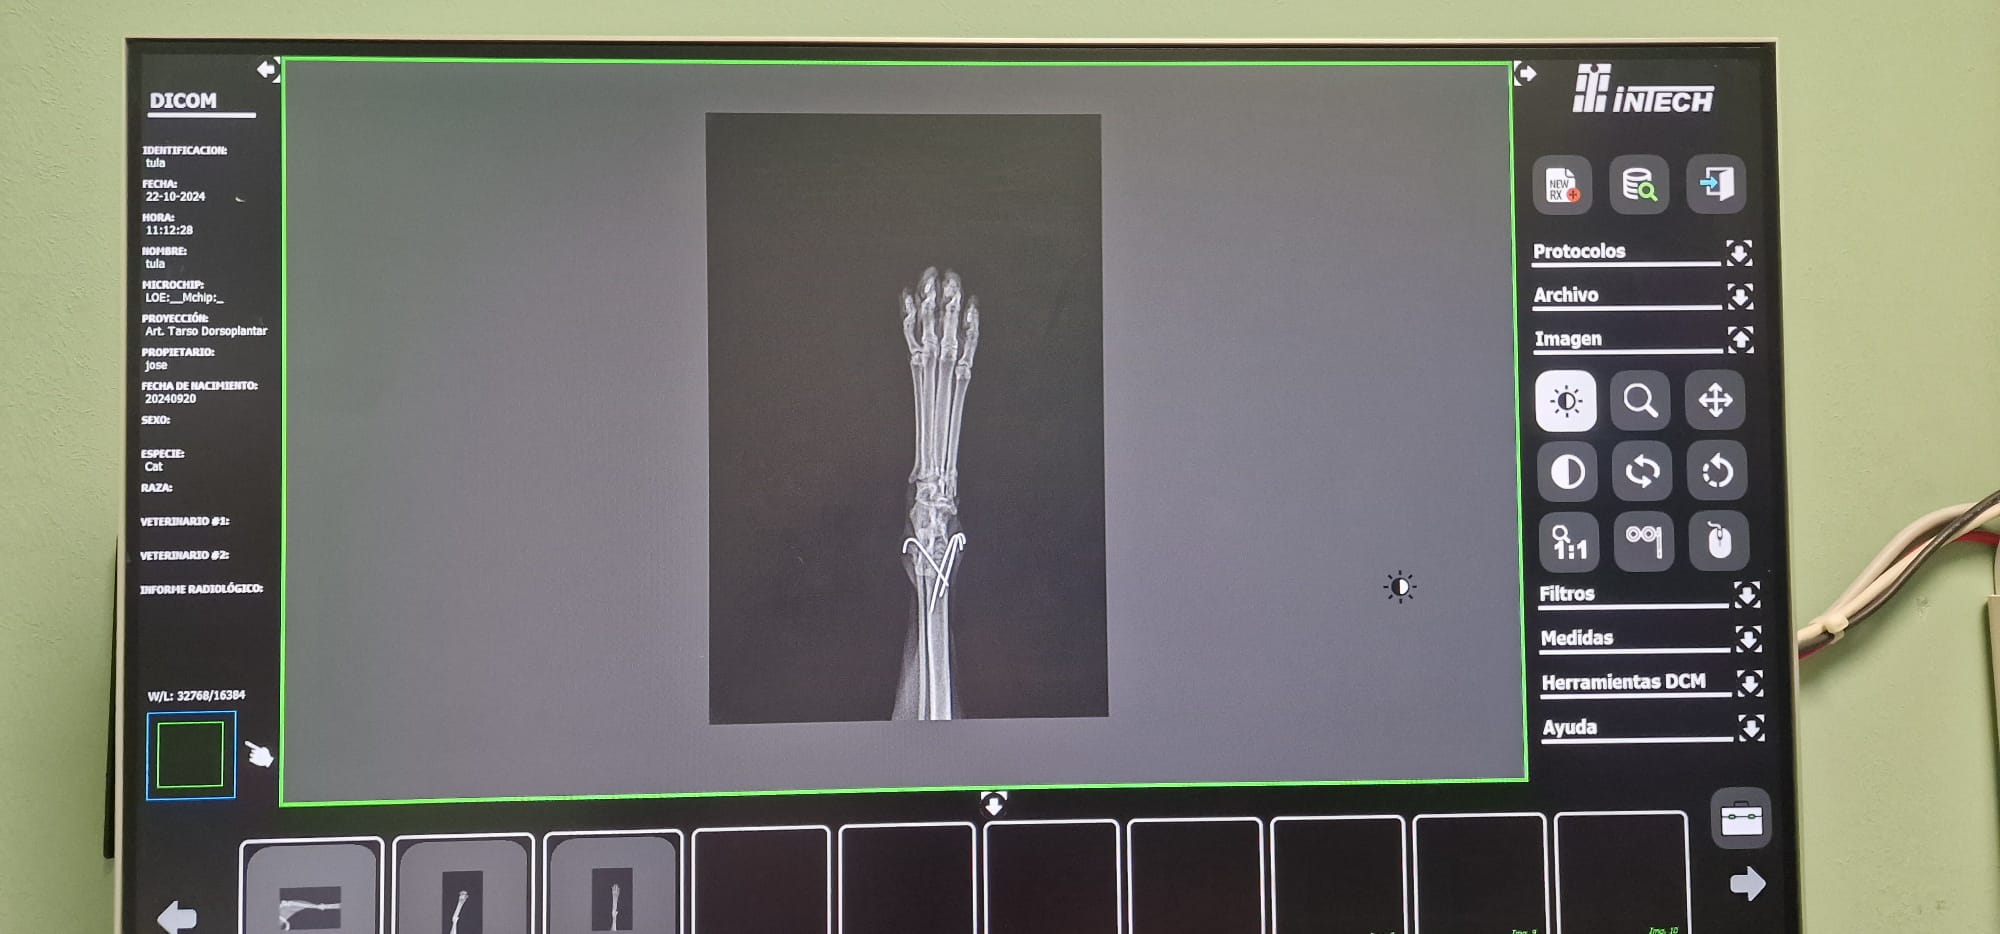

Radiografías = Salud en Imágenes 🐾🩺En Smile Vet, ofrecemos servicios de radiografías para cuidar la salud de tu mascota con precisión y cariño.

• Diagnóstico Rápido: Las radiografías nos permiten detectar problemas (óseos, dentales, respiratorios, cardiacos, etc.) y cuerpos extraños sin procedimientos invasivos. 🐶🐱

• Tecnología Avanzada: Utilizamos equipos modernos para obtener imágenes claras y detalladas, asegurando un diagnóstico eficaz.

• Cuidado Integral: Nuestro equipo interpreta los resultados para ofrecerte el mejor plan de tratamiento, siempre con el bienestar de tu mascota como prioridad. 🐾